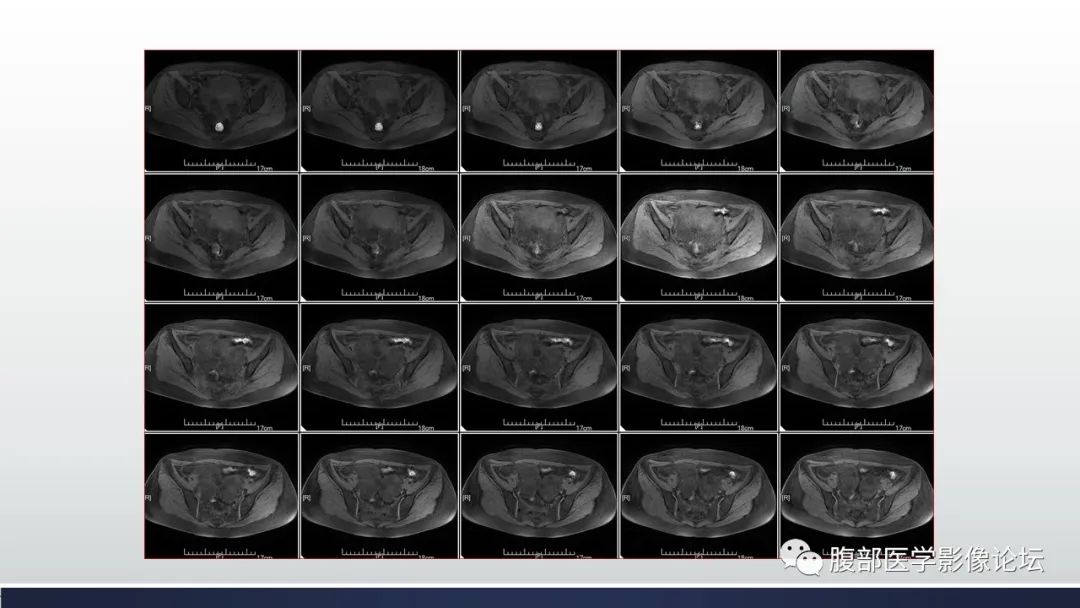

【病例】子宫内膜透明细胞癌1例MR-1

【病例】子宫内膜透明细胞癌1例MR-2

【病例】子宫内膜透明细胞癌1例MR-3

【病例】子宫内膜透明细胞癌1例MR-4